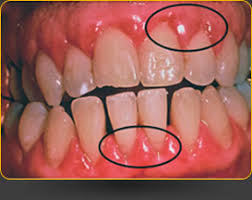

There are a variety of options available each with different ingredients correctly used to reduce the bacteria in your mouth. This form of gum disease does not include any loss of bone and tissue that hold teeth in place. If in the early stages gingivitis you can reverse the disease.

Treated it can advance to periodontitis which means inflammation around the. Is It Possible To Reverse Periodontal Disease. Yes gum disease can be reversed.

Like any serious health condition early treatment is key to successful treatment and periodontal disease is no exception. Periodontitis cant be reversed only slowed down while gingivitis can be reversed. Periodontal disease is one of the leading causes of tooth loss.